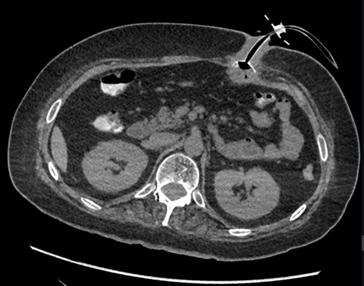

- CT:

- Will identify internal bumper located outside of gastric lumen, may have surrounding soft tissue thickening, inflammatory changes, or abscess formation

- Provides detailed anatomical localization

- Allows for assessment of possible complications (abscess formation, perforation…)

- Contrast study should be performed prone as contrast may falsely appear to safely pass through the imbedded bumper into gastric lumen

- Axial CT image of buried bumper

Image source : https://doi.org/10.53347/rID-148034

Figure 3. Axial CT Image, baby bumper